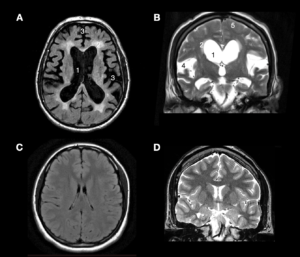

iNPH je onemocnění, při kterém dochází k poruše dynamiky mozkomíšního moku a postupnému rozšíření mozkových komor (Obrázek 1). Přesná příčina tohoto stavu není dosud zcela objasněna, za pravděpodobný mechanismus je však považována porucha cirkulace a resorpce mozkomíšního moku, vedoucí k chronické dysregulaci likvorové dynamiky a postupné dilataci komorového systému. Na rozdíl od akutních forem hydrocefalu ale nejde typicky o dramatický stav s obrazem nitrolební hypertenze (tedy bolestmi hlavy, nauzeou nebo poruchou vědomí). iNPH se rozvíjí pomalu, plíživě, dlouho může působit nenápadně a navíc se vyskytuje v seniorské populaci — právě proto bývá v klinické praxi snadno zaměněn za jiné poruchy vyššího věku.1,5

Obr. 1: Typický obraz iNPH (A,B) v porovnání se zdravým, středně dospělým člověkem (C,D) na magnetické rezonanci (MRI). Na horních dvou obrázcích jsou vidět charakteristické změny u pacientů s iNPH, které jsou zejména (1) výrazné rozšíření mozkových komor, tzv. ventrikulomegalie, (2) periventrikulární hypersignalita, která poukazuje na fenomén transependymálního přestupu, tedy stavu, kdy v důsledku zvýšenému tlaku v komorách přechází mok z komor do okolního parenchymu, ten je díky tomu „prosáknutý”. (3) Výrazná atrofie mozkové tkáně. (4,5) Rozšíření subarachnoidálního prostoru zejména v oblastech Sylviovy rýhy, naopak jeho zúžení na konvexitě včetně kompresí okolních mozkových drah. Zdroj: archiv autorky (pro zvětšení rozkliknout)

Diagnóza iNPH se neopírá o jediné klinické ani jediné zobrazovací vyšetření, nýbrž o soubor vzájemně se doplňujících nálezů. Základ tvoří typický klinický obraz, zejména porucha chůze, kognitivní změny a porucha kontinence, který je následně konfrontován s nálezem na zobrazovacích metodách, především na MRI mozku. MRI umožňuje posoudit přítomnost ventrikulomegalie a dalších charakteristických morfologických známek iNPH, současně však pomáhá vyloučit jiné příčiny pacientových obtíží (Obrázek 1). Samotný zobrazovací nález však k definitivnímu rozhodnutí nestačí, protože podobné strukturální změny mohou být přítomny i u jiných stavů vyššího věku. 1,9